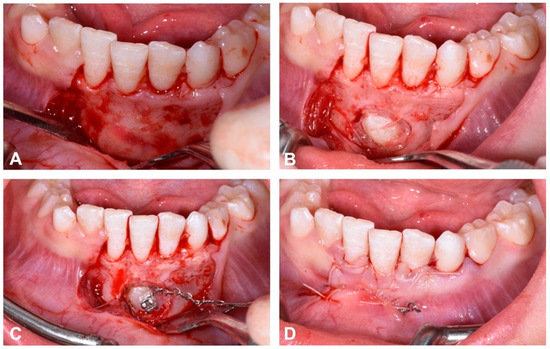

The surgical exposure of the affected canine was performed with a full thickness flap. A bone incision was then made at the level of the cusp of the canine until two thirds of the crown was exposed. A bracket, to which a metal chain with traction loops had previously been welded, was applied using an adhesive technique. The visible part of the tooth crown was first etched with 37% phosphoric acid and the bracket was bonded with a light-curing adhesive system (Transbond XT, 3M Unitek, Monrovia, CA, USA). At the end of the surgical procedure, the flap was repositioned with a resorbable Nytilon 4.0 suture and one eyelet of the ligature was left on the surface to be used for overhead traction (Figure 8).

Figure 8. Flap opening (A); surgical exposure of the buccal side of impacted crown’s canine (B); positioning of the metal bracket for orthodontic traction (C); flap repositioned with resorbable suture and visible traction ligature (D).